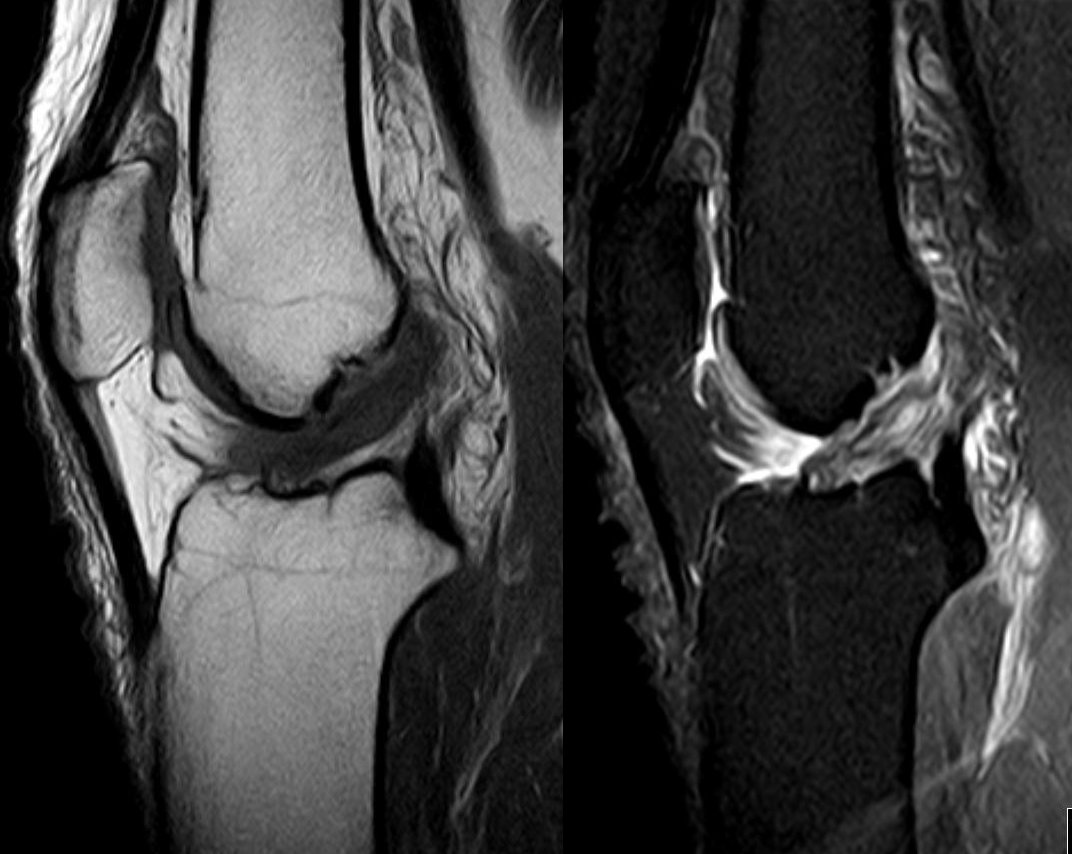

Normal knee phantom with intact bone, cartilage, menisci, and ligaments for baseline comparison

Knee with complete ACL rupture showing torn ligament, bone bruises on lateral femoral condyle and posterolateral...

Knee with medial meniscus tear (bucket-handle type) showing displaced meniscal fragment, joint effusion, and...

Degenerative knee with joint space narrowing, osteophytes, subchondral sclerosis, cartilage thinning, and Baker's cyst